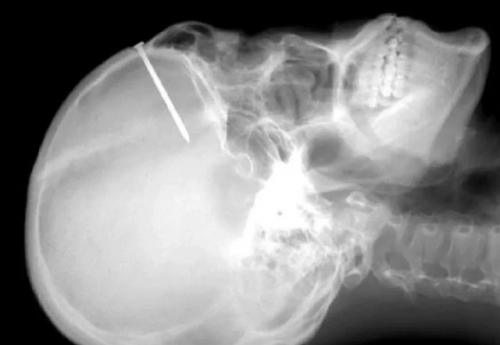

В прошлом у пациента были эпизоды депрессии, расстройства личности и попытки преднамеренного самоповреждения. Однако в последнее время он чувствовал себя хорошо. Мужчина регулярно обрабатывал раны антисептиком и скрывал их под головным убором. За два дня до того, как обратиться в больницу, он забил гвоздь длиной 12, 7 см, что значительно превышало размеры предыдущих гвоздей

.